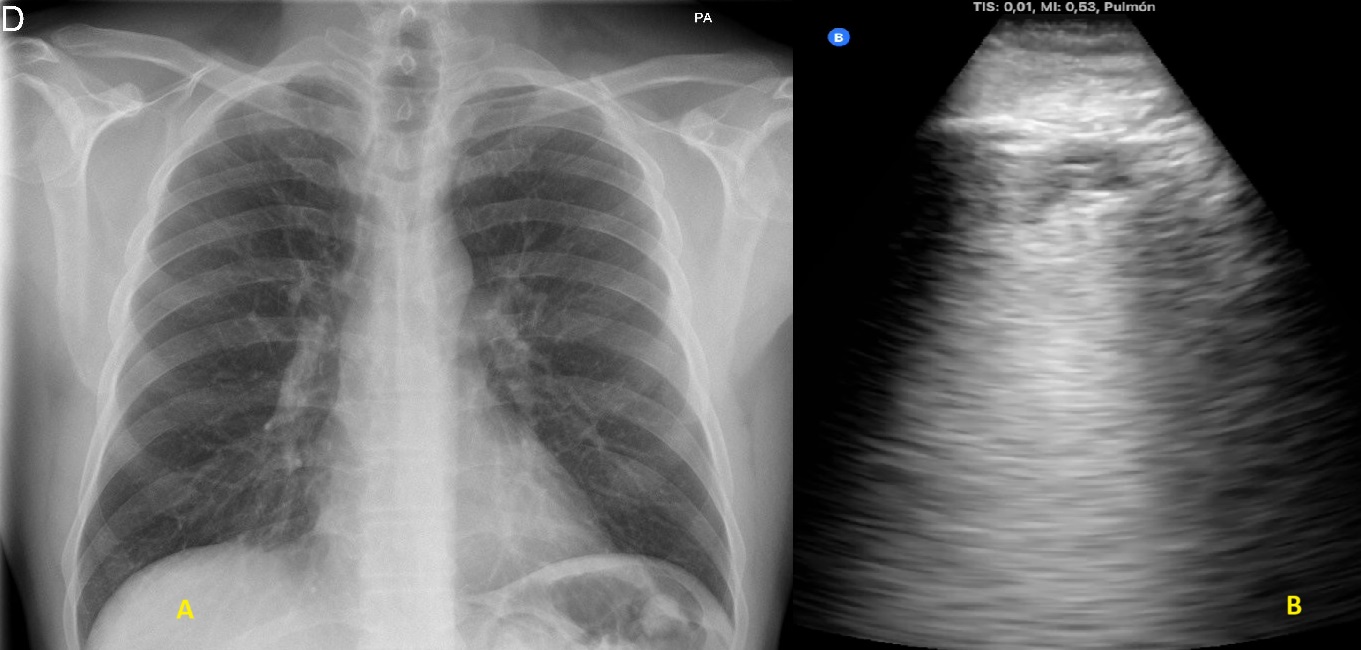

2. Radiografía de tórax con consolidación en lóbulo medio tras los hallazgos ecográficos (figura 4).

2. Consolidación de mayor tamaño (figura 2), con zonas de pulmón blanco y líneas B confluentes adyacentes a la misma (figura 3), en zona anterior y lateral derechas. Se vuelve a auscultar apreciando sólo leve disminución de murmullo vesicular en la zona.